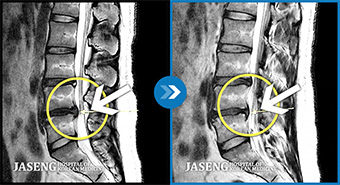

협착증의 치료는 증상의 정도에 따라 보존적 치료와 수술적 치료로 나뉩니다. 대부분의 환자는 보존적 치료로 증상을 개선할 수 있습니다.

보존적 치료로 3개월 이상 호전이 없거나, 진행성 신경 손상, 심한 보행 장애가 있는 경우 수술을 고려합니다. 척추관 확장술(감압술)이 일반적입니다.